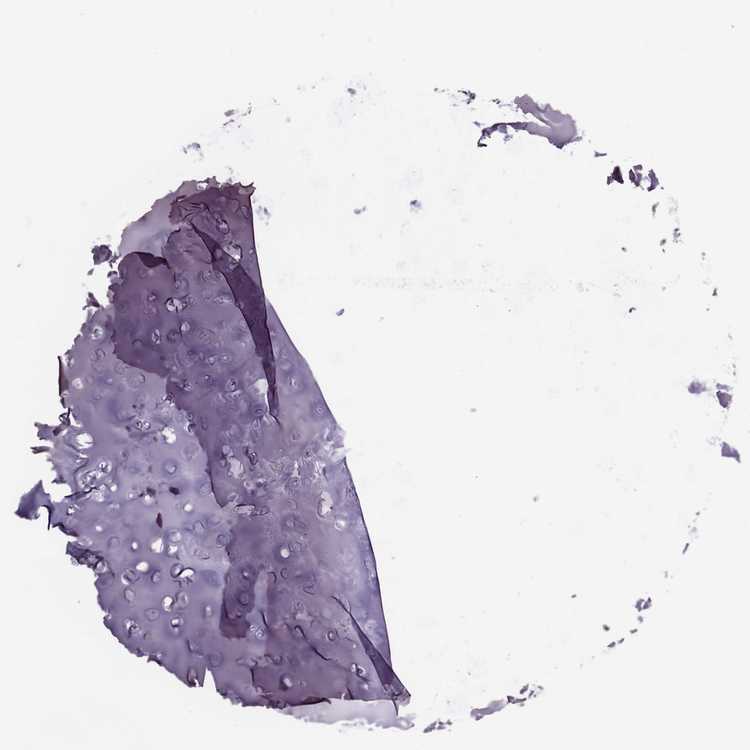

SOFT TISSUE 2 - Antibody stainingi

Antibody staining in the annotated cell types in the current human tissue is reported as not detected, low, medium, or high, based on conventional immunohistochemistry profiling in selected tissues. This score is based on the combination of the staining intensity and fraction of stained cells.

Each image is clickable and will lead to virtual microscopy that enables deeper exploration of all samples and also displays staining intensity scores, fraction scores and subcellular localization as well as patient and tissue information for each sample.

Antibody HPA065718Antibody HPA068266

Fibroblasts Not detectedNot detected

Peripheral nerve Not detectedNot detected